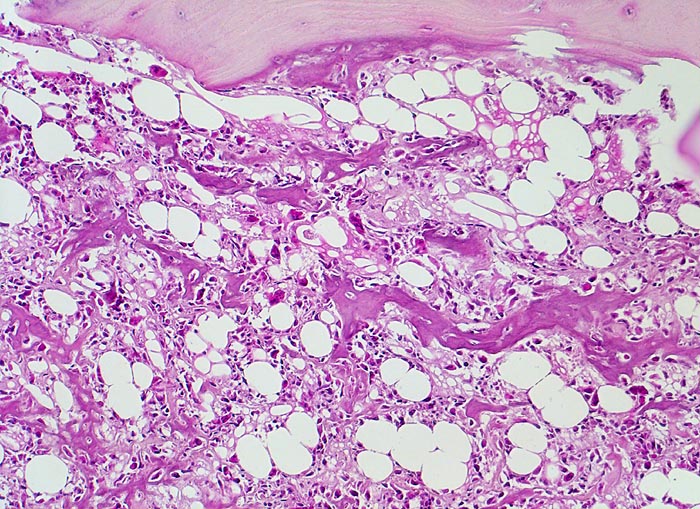

Osteosarkom

Knochen, Femur

Atypische Tumorzellen bilden fein verzweigtes verkalktes Osteoid im ehemaligen Markraum. Neben den Tumorzellen mehrkernige reaktive osteoklastäre Riesenzellen. Oben im Bild erhaltener nicht maligner Lamellenknochen.

16 jähriger Jugendlicher mit seit mehreren Wochen bestehenden belastungsunabhängigen Schmerzen im distalen Femur rechts oberhalb des Knies (Metaphyse). Im Röntgenbild irreguläre Verdichtung, zum Teil auch Aufhellung der ursprünglichen Knochenstruktur mit Zerstörung der Corticalis und spiculaartige (=sonnenstrahlenähnliche) Periostreaktion. Im Serum erhöhte alkalische Phosphatase.

Histologie

100